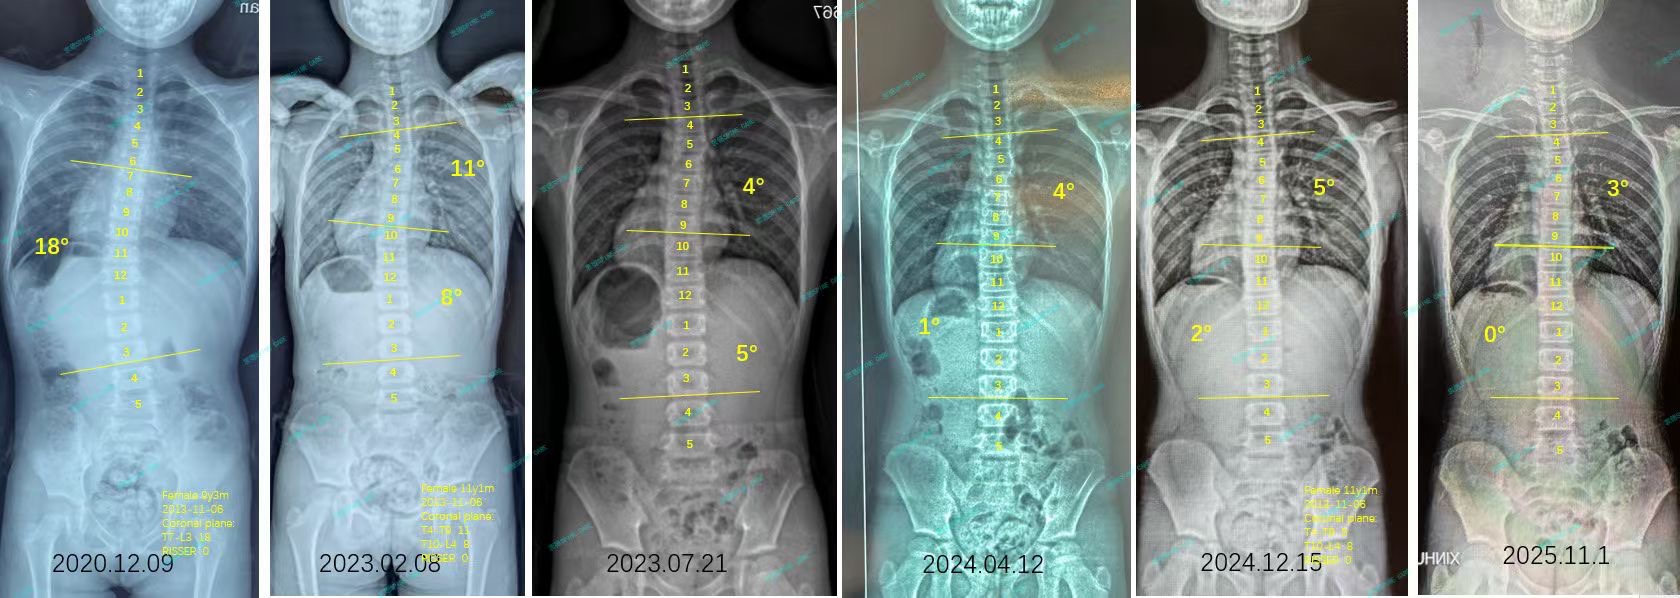

你好,我叫娴娴,发现脊柱侧弯的时候我7岁,当时爸爸妈妈都没想到那么小的我会有脊柱侧弯,于是赶忙带我到公立医院去康复。但是随着时间流逝,我虽然康复很认真,但是侧弯反而越来越严重,来到衷德的时候,杨博士测量我的侧弯已经18度了。

Hello, my name is Xianxian. I was 7 years old when I discovered scoliosis. At that time, my parents didn't expect me to have scoliosis at such a young age, so they hurriedly took me to a public hospital for rehabilitation. But as time passed, although I was very serious about my recovery, my scoliosis became more and more serious. When I came to Zhongde, Dr. Yang measured that my scoliosis was already 18 degrees.

于是在爸爸妈妈的一番搜索后,我们选择了衷德脊柱侧弯矫正与研究中心。在这里训练比医院里让我更自在,有耐心的康复师姐姐,有音乐,我也能一边听自带的故事一边训练。因为我一直都非常认真,所以再次拍片的时候也终于看到了良好的结果,我的18度侧弯下降到了8度!完全恢复到了正常范围内。这是非常让我感到开心的一件事~

So after some searching by my parents, we chose the Zhongde Scoliosis Clinic and Research Center. Training here makes me more comfortable than in the hospital. With my rehabilitation therapists and music, I can also train while listening to my favorite Harry Potter stories. I have always been very serious on my training, so I finally saw good results when I took the x-ray again. My 18-degree lateral curvature dropped to 8 degrees! It has completely returned to normal range. That makes me very happy ~

由于我年纪还小,爸爸妈妈决定让我继续在衷德做训练,每周一次的训练我也认真对待,我一定要维持住现在的健康脊柱,不让它重新变弯。

Since I am still young, my parents decided to let me continue to train in Zhongde. I also take the weekly training seriously. I must maintain my healthy spine and prevent it from turning curved again.

最近的拍片结果显示我的侧弯又好转了一些,现在已经0度啦~为了感谢衷德团队的帮助与陪伴,我送给他们一幅画,谢谢你们让我保持健康~

The recent x-ray results show that my scoliosis has improved a little more, and now it is already 0 degree ~ To thank Zhongde's team for their help and company, I drew them a painting. Thank you for keeping me healthy ~